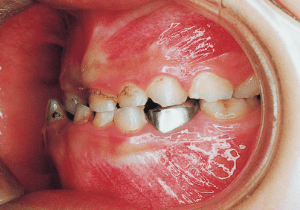

15 Beginning of 2nd Phase 1-29-’97 15 years 6 month

16 Before surgery 7-21-’98 17 years

17 After surgery 8-11-’98 17 years 1 month

22 After treatment 2-10-’99 17 years 7 month

23 After Retention 1-22-’01 19 years 6 month

Although early treatment improved the slight deviation observed during the deciduous dentition stage, it became apparent that the deviation increased with age, eventually exceeding the limits of treatment. This appears to be an innate deviation, and the developmental pattern observed in this case seems to disregard the occlusion. Four first premolars were extracted (15), crowding was corrected and space closure was performed (16), and surgical intervention improved the deviation (17).